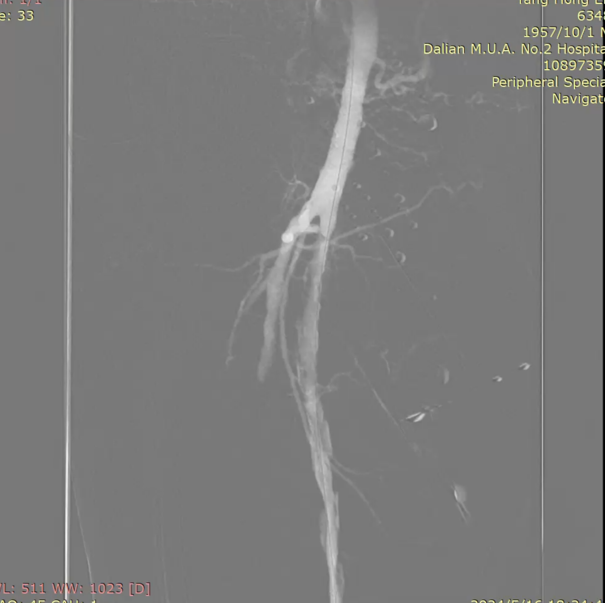

★ CASE 4 近穿刺点植入覆膜支架—假性动脉瘤支架感染

图为:右侧穿刺点附近,造影剂外渗

DSA下于髂分动脉叉处预置球囊阻断,大量炎性组织包裹血管,大量脓汁流出,血管破损严重,支架远端外露,向近心端探查血管,管腔感染明细

右侧腹直肌外侧切开皮肤,进入腹膜探查见髂总动脉起始端向远心端均见明显炎性改变,质脆,无法完成结扎阻断且覆膜支架与组织黏连无法取出

处理:以Hem-lock夹毕股动脉远端覆膜支架,充分止血,缝于周围组织固定,万古霉素2g撒于切口内,留置引流,vac覆盖切口。